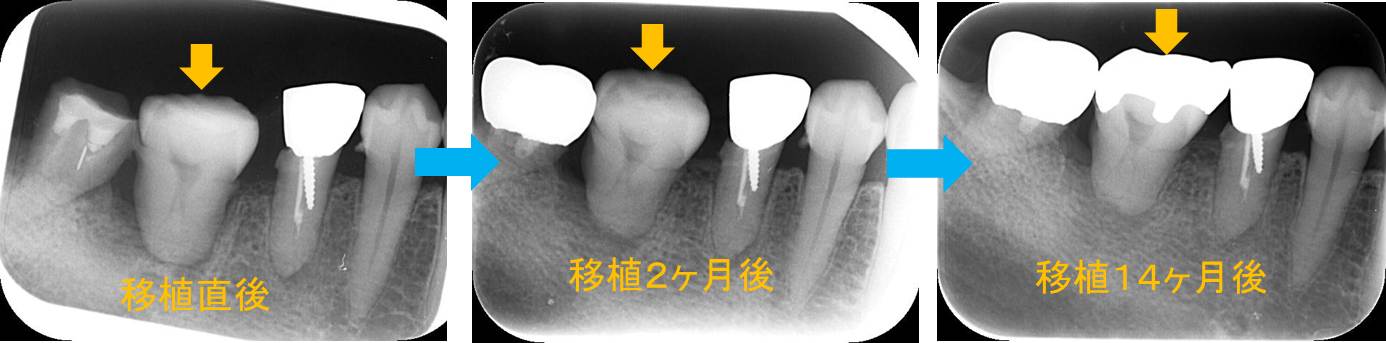

次にデンタルエックス線撮影で細かく見ていきます。

左から移植直後→移植2ヶ月後→移植14か月後です。

移植2ヶ月後に歯周ポケット検査を行った結果、遠心(奥側)に9mmの歯周ポケットが認められました。何回か超音波スケーラーとイソジンによるポケット内洗浄を行いましたが改善しませんでした。そこで、SRPを行った結果、1ヶ月後に歯周ポケットが消失しました。

歯の周囲にある歯根膜という組織(30μmくらいのフィルム)があり、その組織が移植の成功の鍵を握っています。その組織に骨、セメント質などを再生してくれる細胞があります。つまり親知らずを抜くときにできるだけ歯根膜は損傷してはいけません。今回は、上手くSRPで対応し歯周ポケットが改善しました。

また、今回の移植は「歯の神経」が術後も生きていました。ほとんどの場合は、移植後に歯の神経が死んでしまい根管治療が必要になりますが、今回は神経が生きていたため根管治療を行う必要はありませんでした。